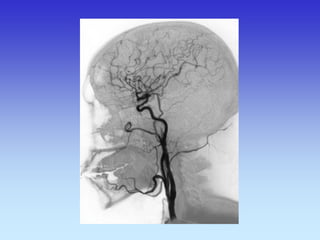

METODE PRIKAZA KRVNIH ŽILA

•DSA

VASKULARNA OPSKRBA WILLIS-ijev prsten

a. cerebri ant.

a. cerebri media

a. cerebri post.